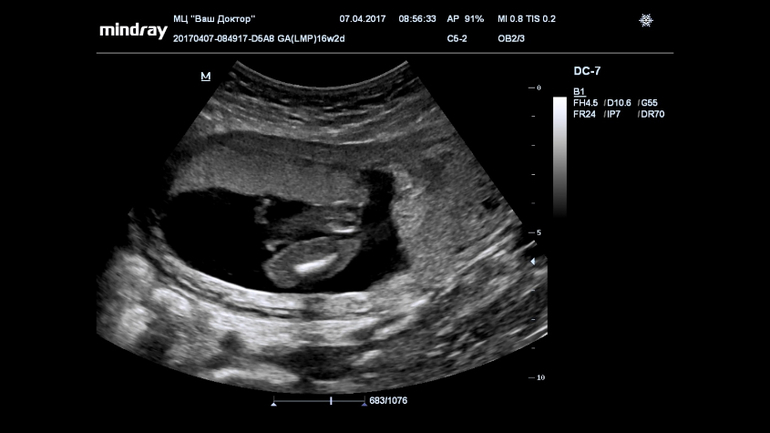

Ну девчуля же? Кто разбирается?

Пол малышаВсе 16 недель была просто уверенна, что в домике живет сыночка, а тут на УЗИ огорошили, что у нас там девица-красавица! Я конечно прибываю в небольшом шоке, но БЕЗУМНО этому рада!!!!!

Записали нам диск, все выходные пересматривала, сделала несколько фото, что скажете?